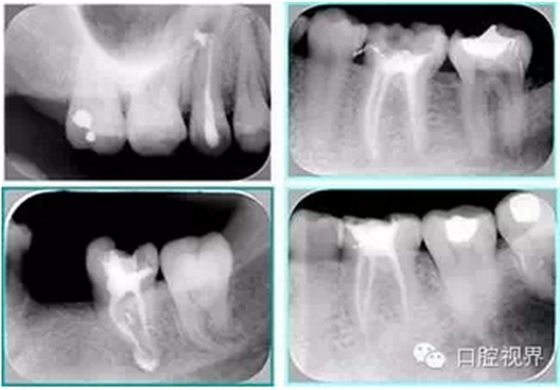

左圖和上圖為干髓治療后牙齒,齲齒疏通后進行根管充填。

如圖為塑化加根充處理后牙齒 X 線片。

常見有修復性鈣化和增齡性鈣化。下面為根管鈣化 X 線片。